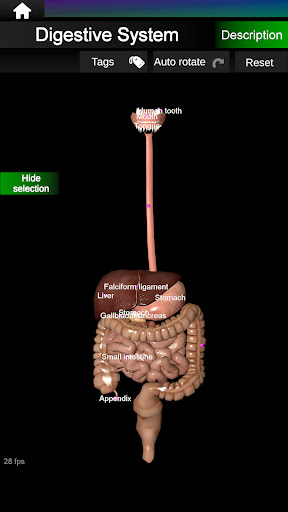

* Spijsverteringsstelsel, inclusief de maag, dunne darm, dikke darm, en een animatie van dit systeem.

* Gemakkelijk te openen en te navigeren (zoom, 3D-rotatie).

* Verberg of toon informatie.

* Beschrijvingen van elk orgel.